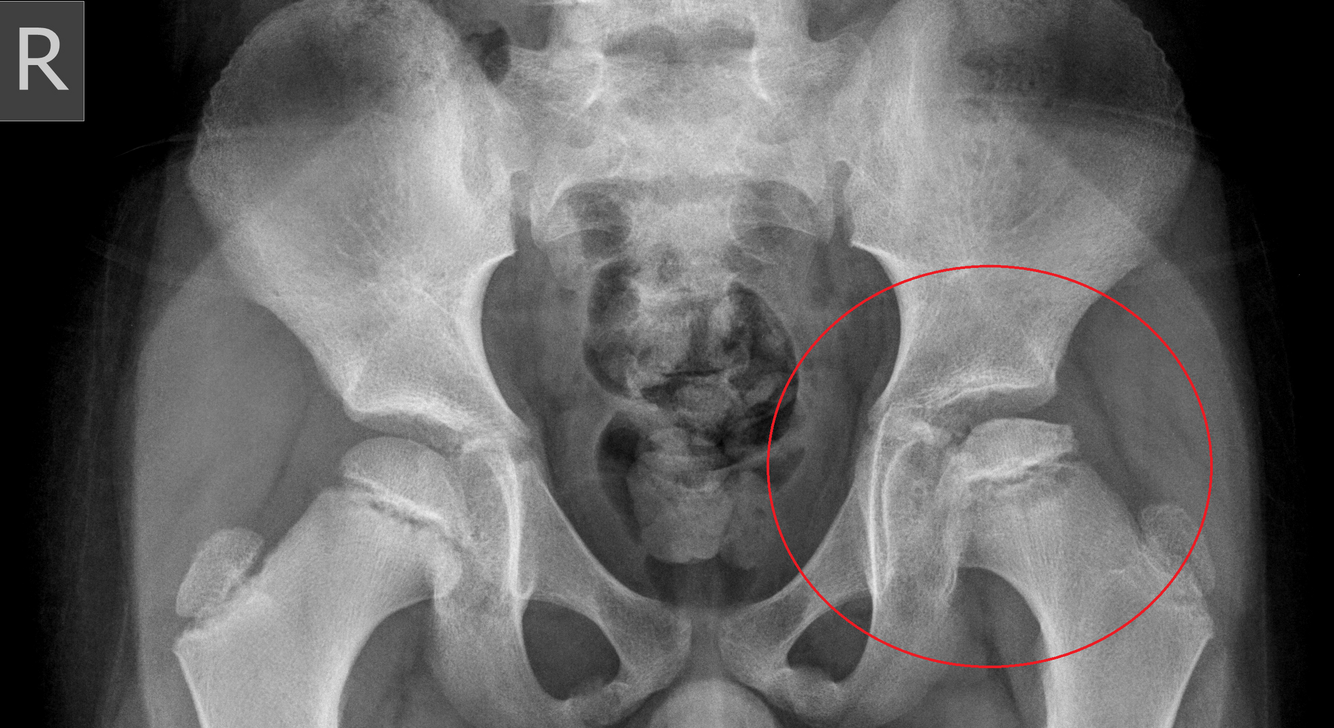

Early plain x-ray changes in Perthes Disease:

Widening of the joint space.

Sub chondral linear lucency.

Idiopathic avascular necrosis of the femoral head.